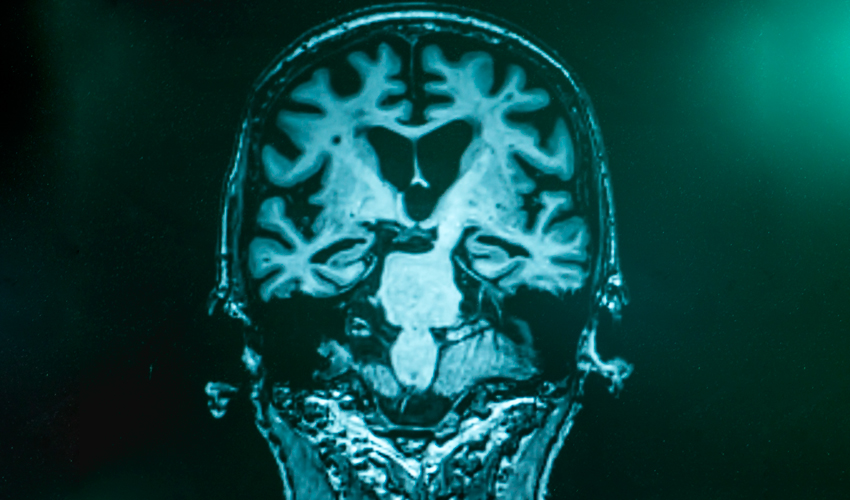

Klinik och vetenskap Frontotemporal demens